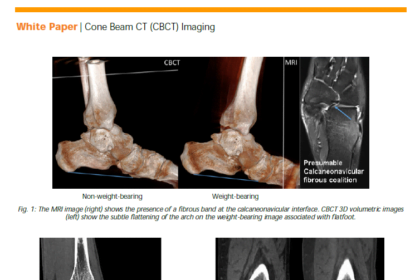

White Paper: 3D Weight-Bearing Imaging Using CBCT

This white paper addresses the benefits of a prototype (INVESTIGATIONAL – NOT…